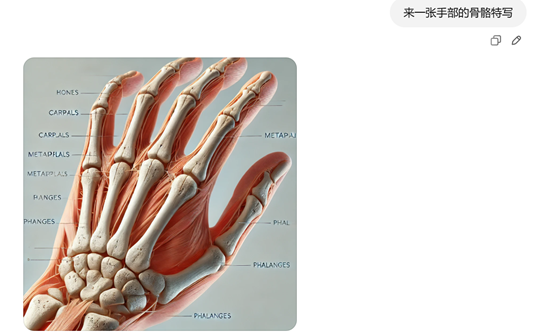

如果不满意,可以基于该图片继续发问,例如,我们想看上面人体介绍的骨骼。提示词:可以详细展示骨骼介绍吗?

我们放大手部骨骼,继续提问:来一张手部骨骼的特写。

需要注意的是,图像的文字介绍可能比较模糊或混乱,这是因为中文提示的原因,如果使用英文会好很多。